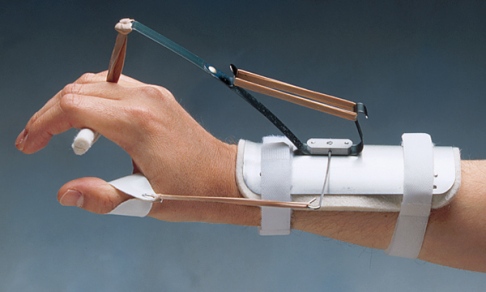

El tratamiento conservador varía de acuerdo con el

nivel y la causa de la neuropatía del nervio radial. Un período de

inmovilización y medicamentos anti-inflamatorios pueden disminuir la

hinchazón y mejorar los síntomas. Además, las férulas funcionales

ayudan a prevenir contracturas y mejorar la función mientras haya

signos de cicatrización del nervio. Por ejemplo, una férula

funcional adecuada para una parálisis alta incluye una férula

de extensión estática para la muñeca y un aparato de extensión

dinámica de las falanges proximales.

Los tratamientos iniciales para el síndrome

del túnel radial y el síndrome del nervio interóseo posterior

son similares. Las férulas y modificación de la actividad ayudan a

limitar la extensión repetitiva del codo, pronación del antebrazo y

flexión de la muñeca. Los medicamentos anti-inflamatorios y la

inyección de cortisona en la zona afectada se utilizan para ambas

condiciones, pero en el síndrome del nervio interóseo posterior, los

músculos debilitados serán protegidos con una férula de dorsiflexión

para la muñeca.